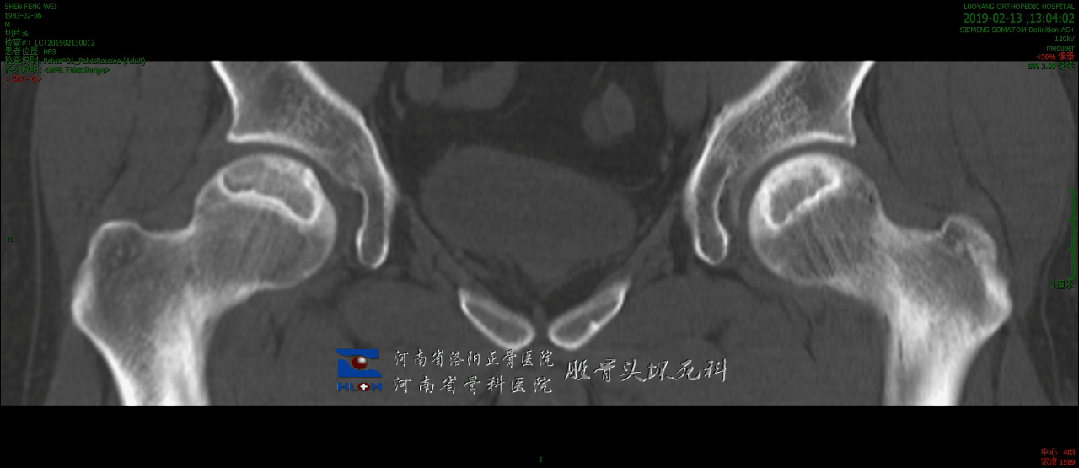

没错,两侧都有大面积的密度减低区,也就是类似于空洞的表现——下一步就是塌陷。

划重点: